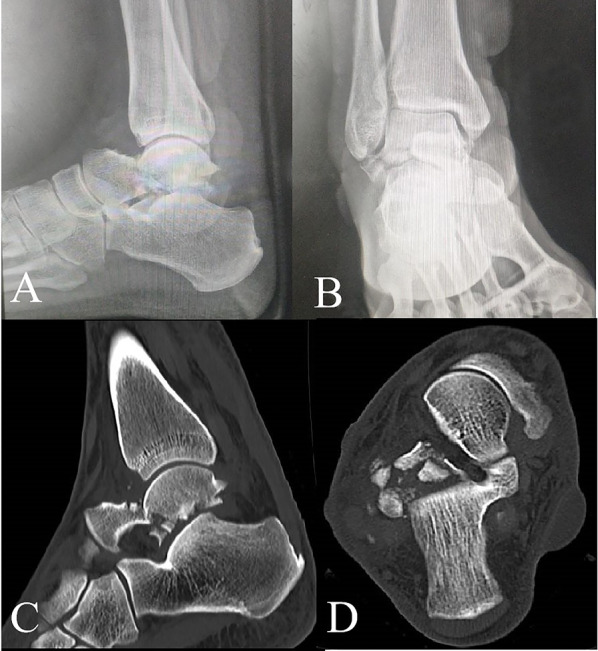

Purpose: To investigate the effect of arthroscopic reduction combined with robot-guided screw placement on Hawkins type II fractures of the talus neck.

Methods: Clinical data from 42 patients with talus neck Hawkins type II fracture treated in the institution from November 2019 to January 2021 were selected. According to the blind envelope method, 21 patients were enrolled in the study group, and 21 patients were enrolled in the control group. The patients in the study group underwent arthroscopy-assisted reduction combined with orthopedic robot navigation screw placement surgery, while those in the control group underwent open reduction surgery.

Conclusions: The management of Hawkins type II fracture of the talus neck using arthroscopy-assisted reduction combined with robot navigation screw placement yields satisfactory results and represents a viable treatment alternative that warrants consideration.